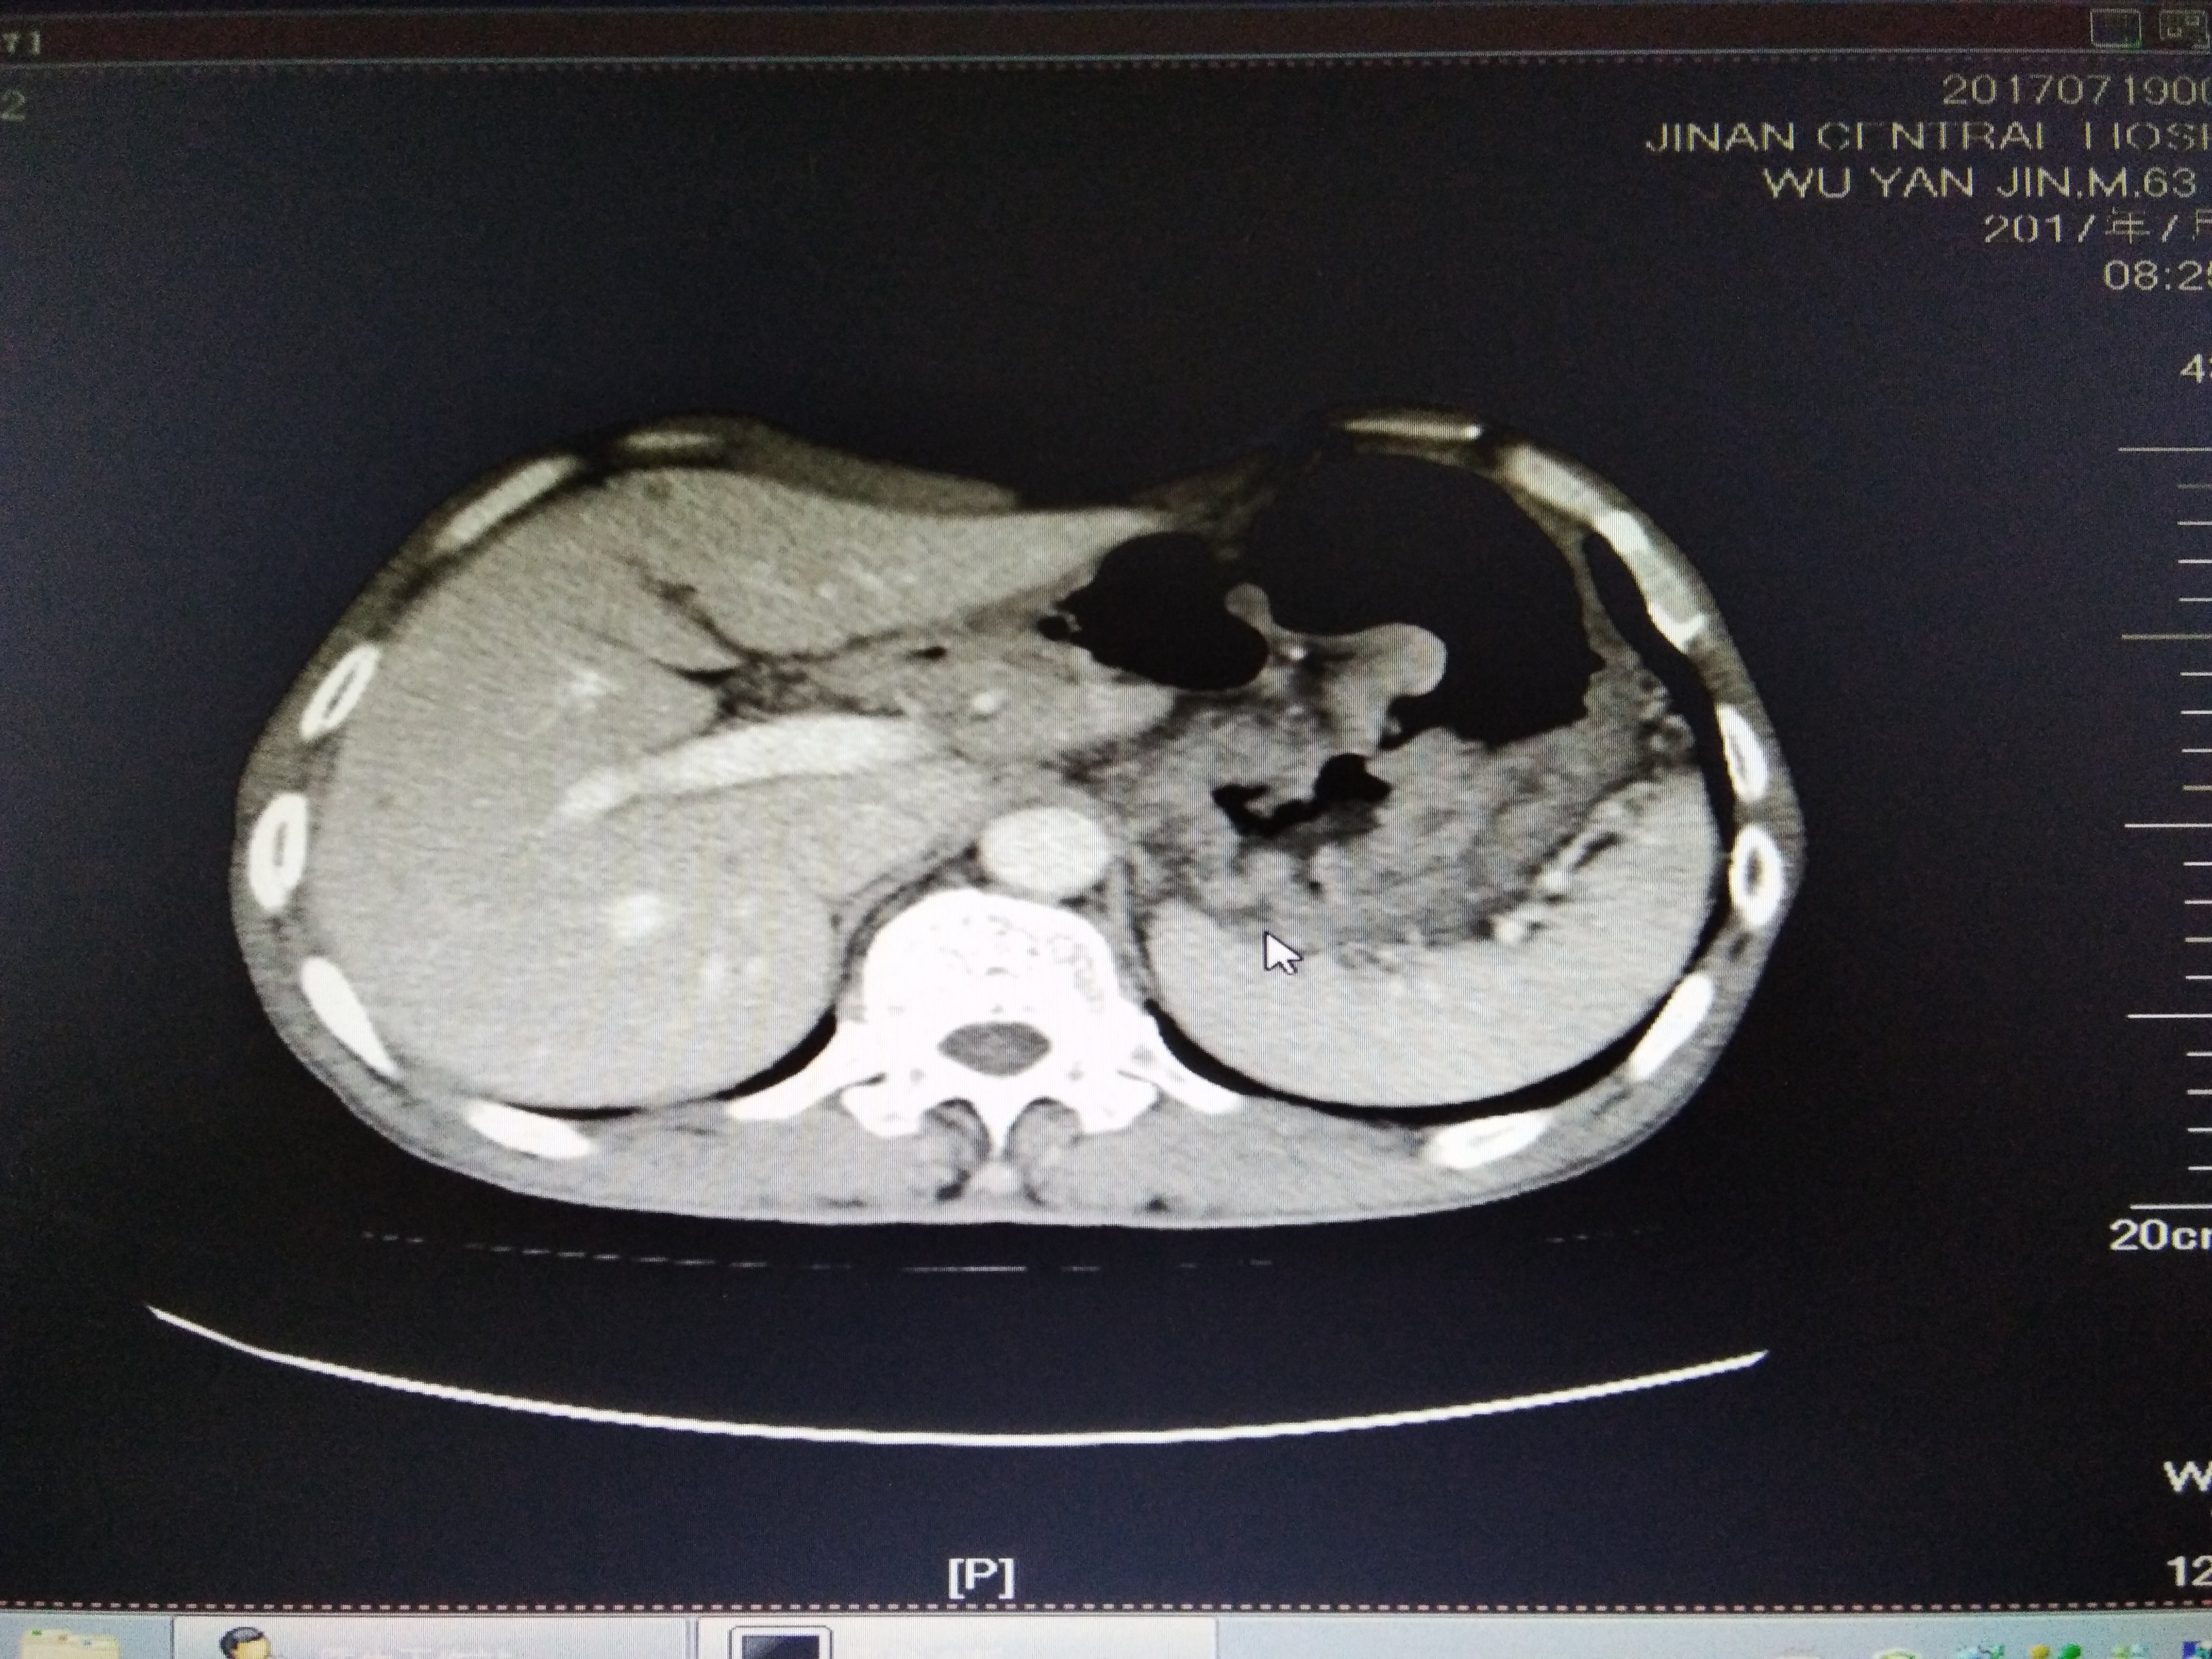

食管贲门癌,肝转移 1,食管贲门处肿块,管壁增厚,管腔狭窄

食管下段贲门癌合并纵膈巨大站位(性质?) [病例帖]